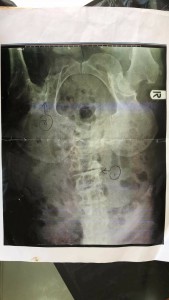

で、送って来たのがこの写真。

左股関節のAVNつまり、左股関節の壊死と訳される。

医師の診断を要約すると

左大腿骨壊死

側湾症

L5と仙骨がくっついている

T11・12は椎骨が骨折していて椎体の前が潰れている

L1〜3は椎間板に骨棘ができている

腰椎に中等度の狭窄があり神経を圧迫している

L4〜5で重度の脊柱管で狭窄が認められる

などなど